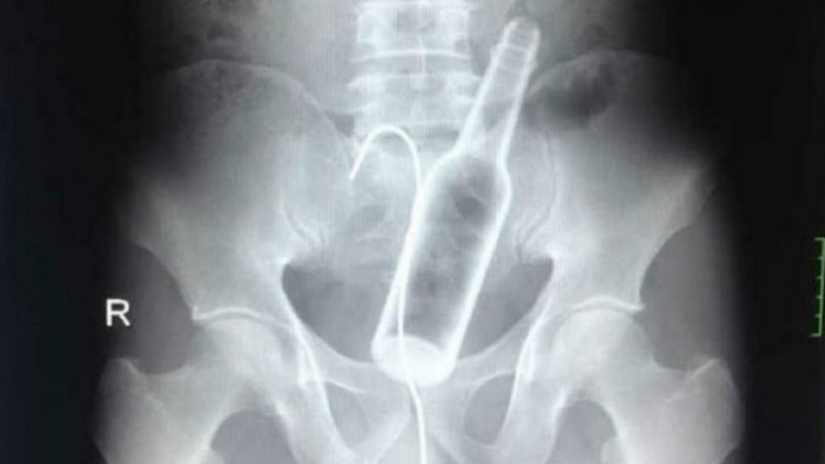

One of the Chinese hospitals, a man came with complaints of abdominal pain. The doctors took an x-ray and found a glass bottle in the stomach.